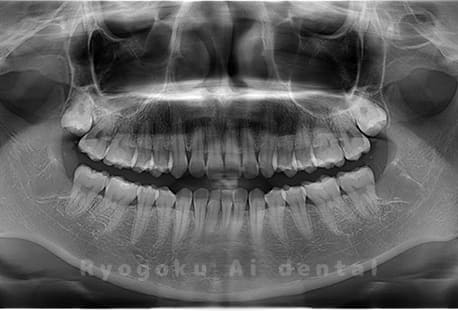

斜めに生えている親知らず

親知らずが斜めに生えて隣の歯にぶつかって圧迫してしまうタイプです。

このタイプが最も多いです。このタイプは虫歯になりやすいだけでなく、隣の歯を圧迫し、咬み合わせや歯並びに影響が出る場合もあるので抜歯をおすすめします。